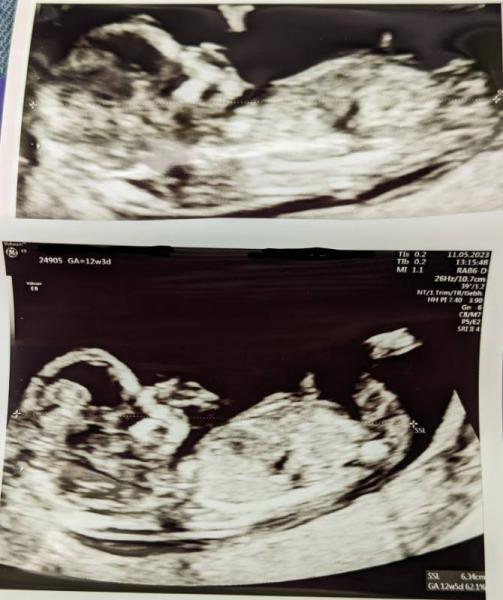

Hallo zusammen, ich war heute beim Ersttrimesterscreening und hab einige Bilder mitbekommen. Uns ist das Geschlecht komplett egal, aber ich bin generell ein soooooo neugieriger Mensch und vorallem ungeduldig :D Vielleicht gibt es hier ja jemanden, der etwas erkennen kann? Mutmaßungen nehme ich auch gerne an. Ist nur so ein kleines Tendenzen Spiel, weil es mich irgendwo auch interessiert, ob man was erkennen könnte. Danke schonmal und liebe Grüße :-)

Huhuu Bin absolut kein Experte und rate auch einfach mal ins blaue (oder pinke), auf dem unteren siehts ein bisschen wie bei uns aus, wo der NUB auf ein Mädchen deutet. Wenns denn ein NUB ist, was ich zu erkennen glaube ;) Also wirklich nur arg spekuliert! Halt uns auf dem Laufenden :)